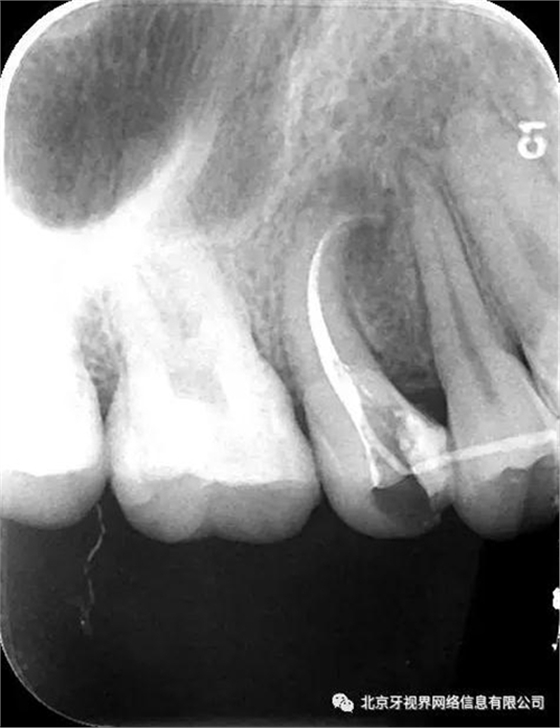

2次復診常規(guī)根備加根充(AH-plus糊劑加牙膠尖根充)

3.操作中切記盲目下針,遇到阻力后冷靜分析(正向阻力與側(cè)向阻力)后,按其彎曲方向緩慢前行,避免形成新的臺階,很多操作中的難度都是術(shù)者盲目下針,用力過大自己造成的。

4.此例病例中,術(shù)前分析后,采取先解放其中上段后,10#擴大器預彎緩慢前行,抵達根尖區(qū)。